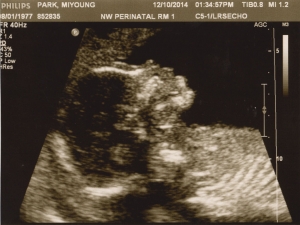

Last Ultrasound